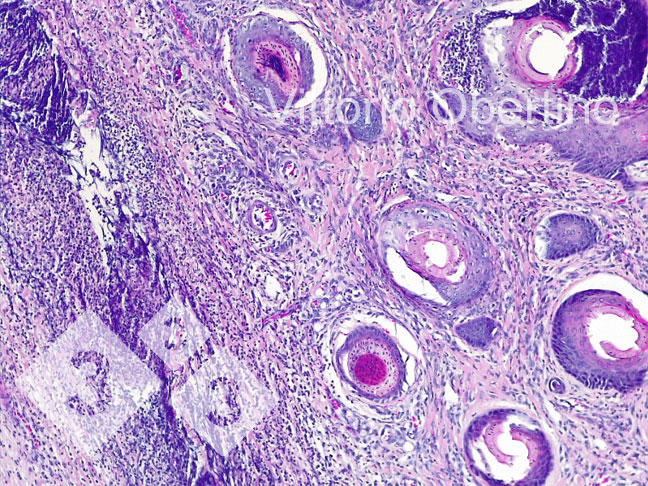

2- Des échantillons de tissus ont été envoyés à l'Université de Turin pour vérifier que les lésions étaient histologiquement compatibles avec les images décrites dans la littérature (Kuehling et al. 2020).

Figure 9. Peau. Érosion épithéliale focale dans laquelle la couche superficielle est remplacée par un matériel éosinophile amorphe à granulaire abondant avec des débris cariorectiques (nécrose) et des granulocytes neutrophiles dégénérés et viables abondants. Multifocalement, l'épithélium apparaît modérément à fortement hyperplasique avec une hyperkératose orthokératosique modérée à sévère. Il existe également une présence multifocale de croûtes. Le derme apparaît diffus et modérément fibreux.